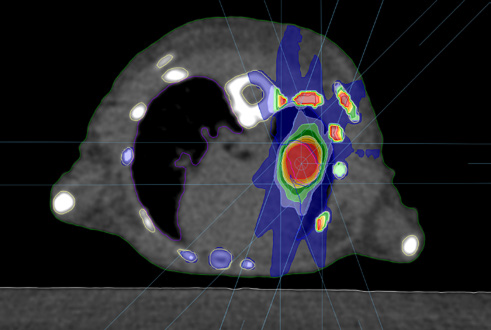

Two irradiation techniques are supported in μ-RayStation: 3D-CRT and static arc. 3D-CRT plans comprise of one or more beams with fixed angles and collimation for each beam (visualization of a beam can be seen in Figure 1. An example of a 3D-CRT treatment plan dose is displayed in Figure 4). Static arc plans comprise of one or more arc beams with fixed collimation and user specified start and stop gantry angles.

Figure 4. An example of a 3D-CRT mouse lung treatment plan consisting of 5 beams (image and plan from Institut Cancérologie de l’Ouest in Nantes, France). The dose calculation grid size is 0.2 mm and the dose uncertainty is roughly 0.5 % for each beam.